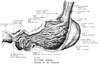

十二指腸【じゅうにしちょう】 The ca. 25-30 cm long segment of the small intestine between the pylorus and duodenojejunal flexure.(十二指腸は胃の幽門から十二指腸空腸曲まで約25cmの腸管。十二指腸Duodenumは12で、intestinum duodenum digitorumの意味。長さが指を12本横にならべた幅に等しいことによる。第1腰椎の椎体右縁の前方ではじまり、C字状に屈曲して膵臓の頭を取り囲む。腸間膜を欠き、後腹膜臓器の一つであり、胆管、膵管が開口するなど他の小腸とは異なる。十二指腸には4部が区別される。上部は幽門につづく5cmの長さの部で、上背外側へはしる。最初の2.5cmは可動性。上縁には小綱が付着する。上十二指腸曲において、ほぼ下方へ屈曲し、下行部(約8cm)へ移行する。その半ばで後内側壁に一条の十二指腸ヒダがり、その下端に大十二指腸乳頭が隆起し、ここに総胆管と膵管が共通に開口する。その上方2~3cmの部に小十二指腸乳頭があることが多く、副膵管の開口をみる。下行部は下十二指腸曲で左方へ屈曲し、水平部(下部、約8cm)へ移行し、第3腰椎体左縁に達し、左上方へ屈曲し、上行部へつづく。この部は約5cm走行したのち、第2腰椎の左方で急に前方に曲がり空腸へ移行する。この部を十二指腸空腸曲という。この曲がりは、横隔膜直下の後大動脈壁から下降する十二指腸提筋で固定されている。十二指腸の前半、ほぼ大小十二指腸乳頭までには、よく発達した十二指腸腺がある。複合管状胞状腺で、分泌物は粘液性でアルカリ性を示すことから胃酸から粘膜を保護するのではないかといわれる。)